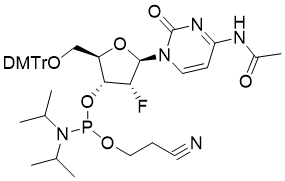

馬鞍山致研生物醫(yī)藥科技有限公司成立于馬鞍山市鄭浦港新區(qū)現(xiàn)代產(chǎn)業(yè)園。公司專(zhuān)注于生物小分子、醫(yī)藥中間體相關(guān)產(chǎn)品的研發(fā)和生產(chǎn),產(chǎn)品主要包括DNA亞磷酰胺單體、RNA亞磷酰胺單體、特殊單體以及按照客戶(hù)要求定制的RNA和DNA,并且公司提供定制合成等方面的研究服...

馬鞍山致研生物醫(yī)藥科技有限公司成立于馬鞍山市鄭浦港新區(qū)現(xiàn)代產(chǎn)業(yè)園。公司專(zhuān)注于生物小分子、醫(yī)藥中間體相關(guān)產(chǎn)品的研發(fā)和生產(chǎn),產(chǎn)品主要包括DNA亞磷酰胺單體、RNA亞磷酰胺單體、特殊單體以及按照客戶(hù)要求定制的RNA和DNA,并且公司提供定制合成等方面的研究服...